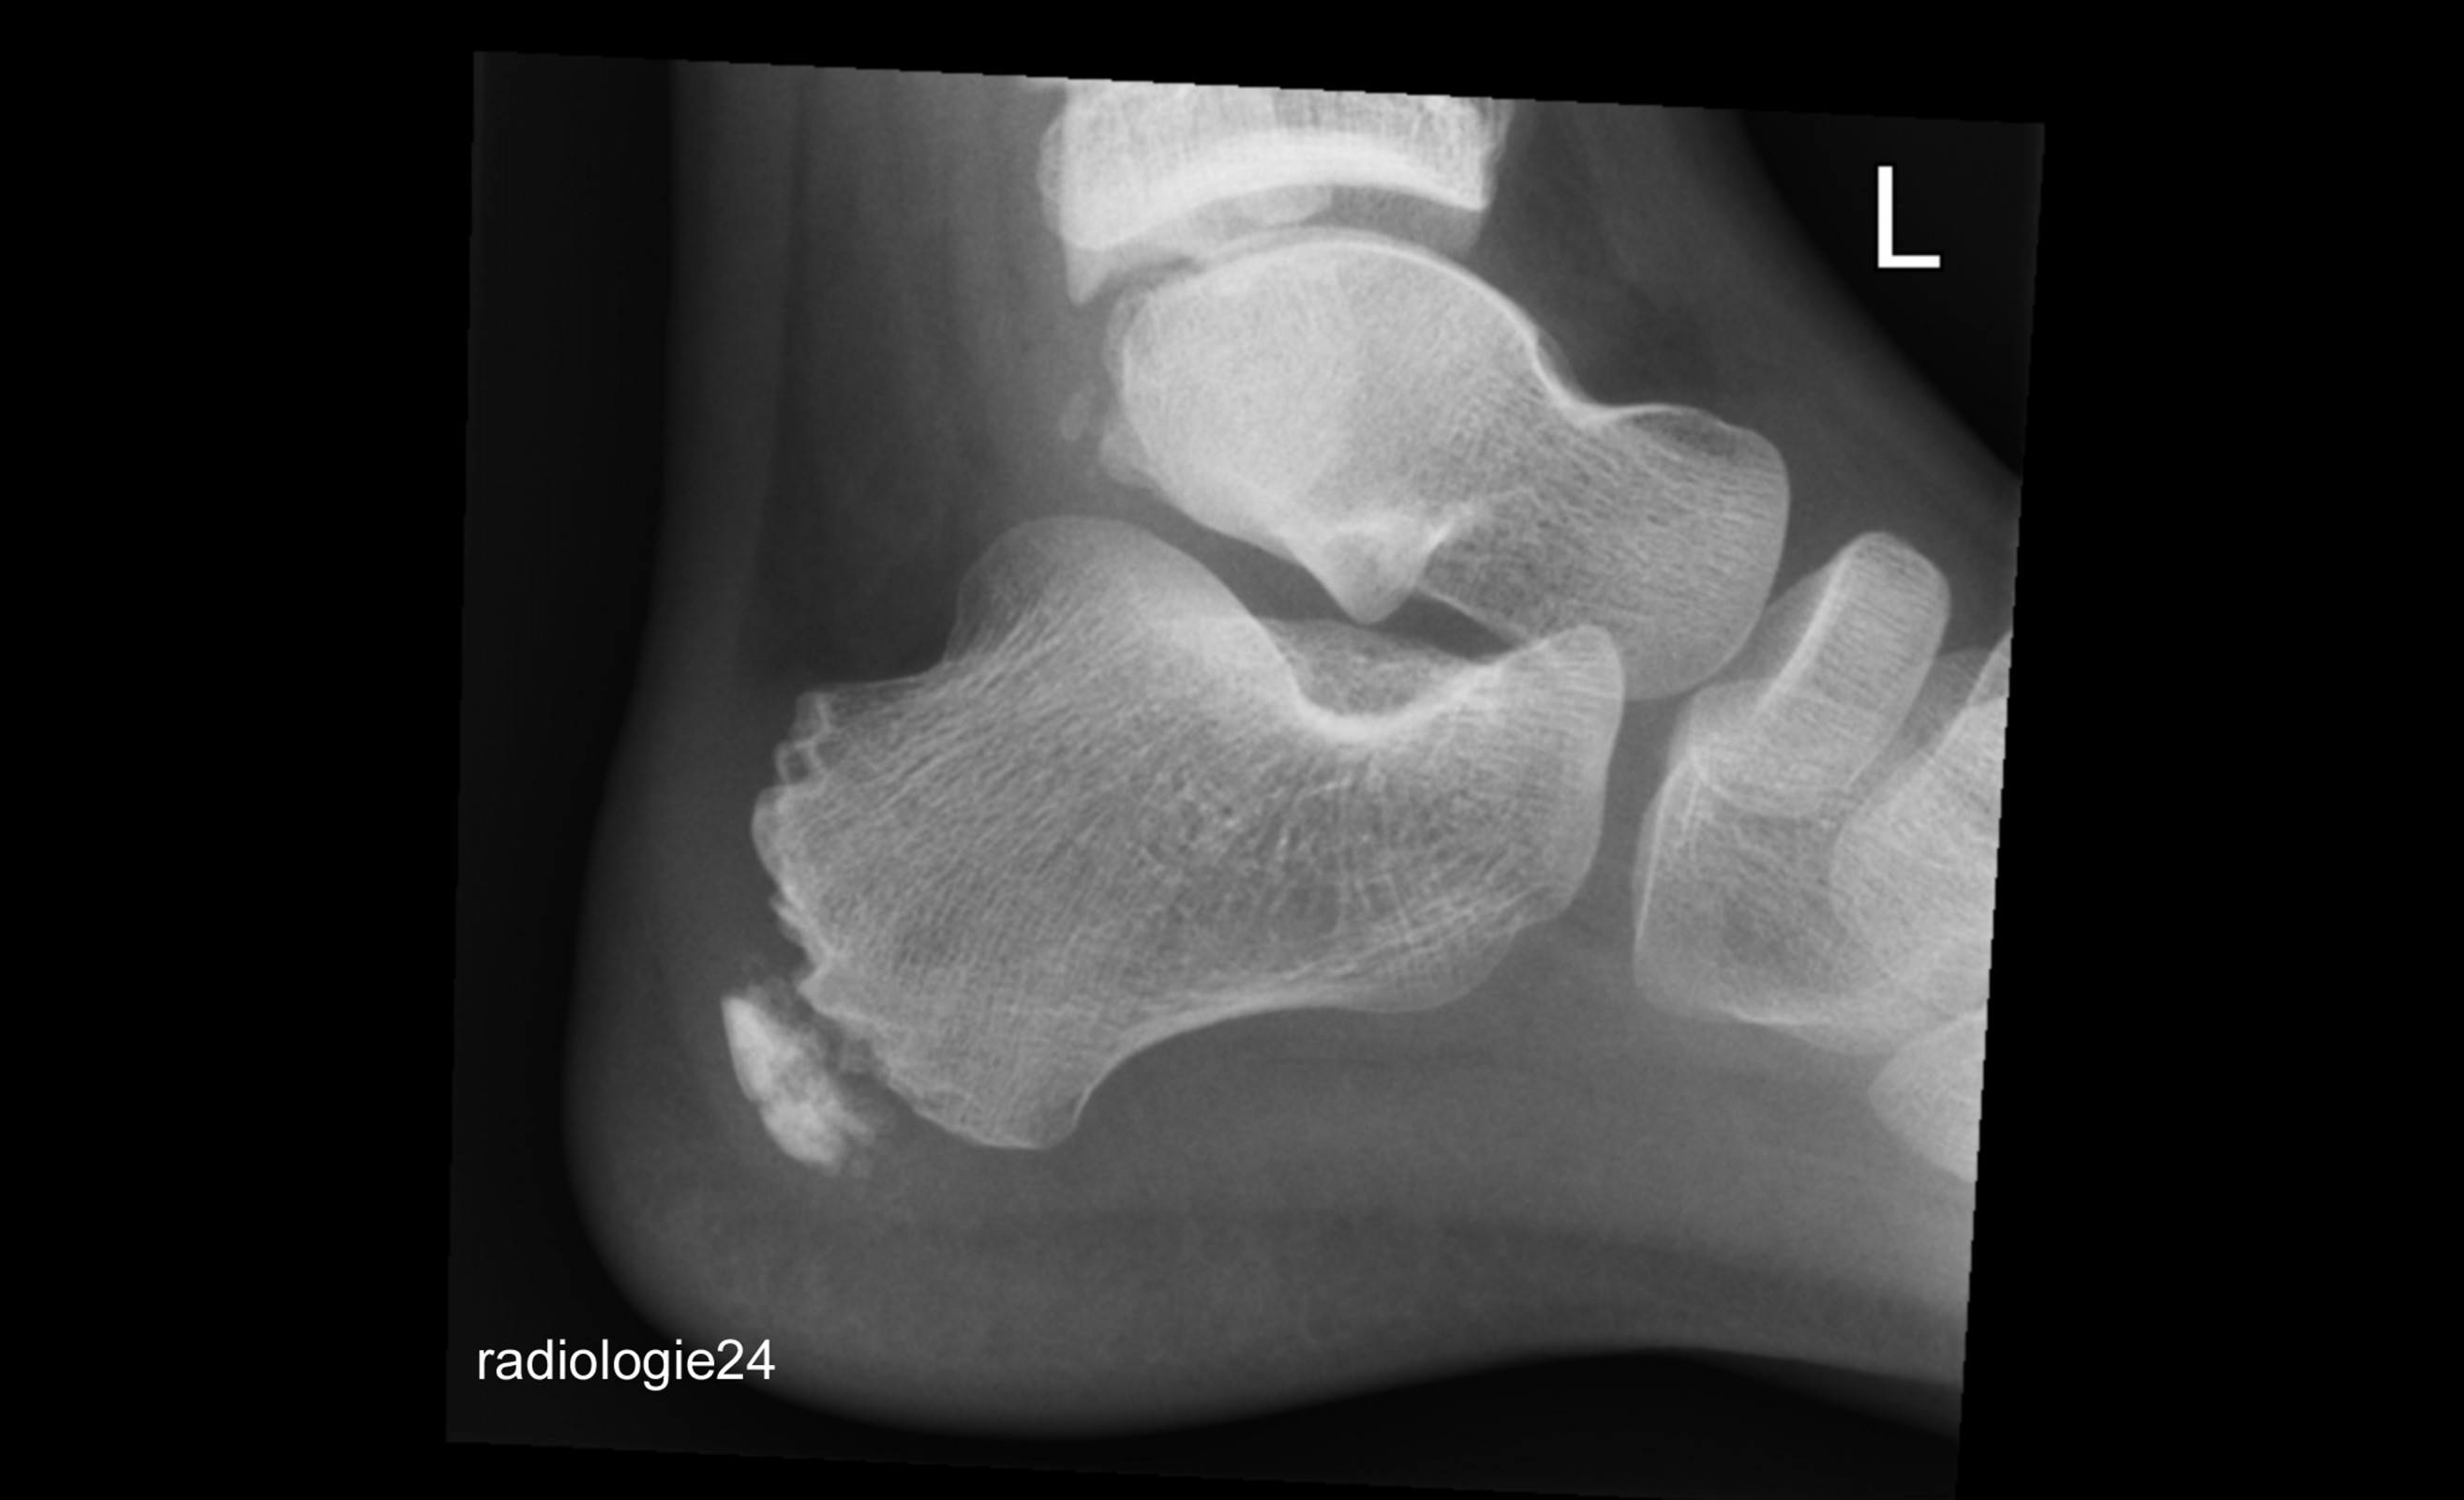

Röntgenfall des Monats April 2018 mit Auflösung

10 jähriger Patient Schmerzen im Bereich des Achillessehnenansatzes nach Fussballspiel. Ihre Diagnose? Weitere Abklärung?

Bild vergrössern

Link zur Auflösung mit ausführlichem Befund:

https://www.radiologie24.ch/radiologie-mediathek/roentgenfall_des_monats